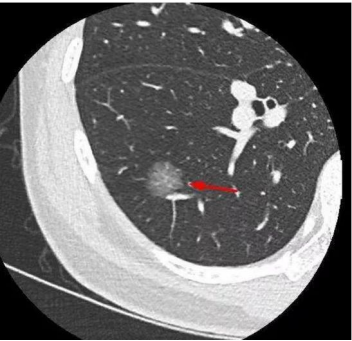

2、如何检测肺部结节?肺结节通常使用肺部CT、X光、MRI和其他仪器进行物理检查。

我院肺结节多专业联合诊疗门诊依托多学科优势,与呼吸与危重症医学、胸外科、医学影像学、以及其他相关部门。基于肺结节的影像学表现,结合吸烟、肿瘤家族史及相关临床症状等高危因素,整合多学科资源进行综合评价,解答肺结节患者心中的疑虑,减轻心理负担,发展更全面、规范、专业、准确的诊疗方案,达到早发现、准确诊断、及时治疗、正确治疗的目的。